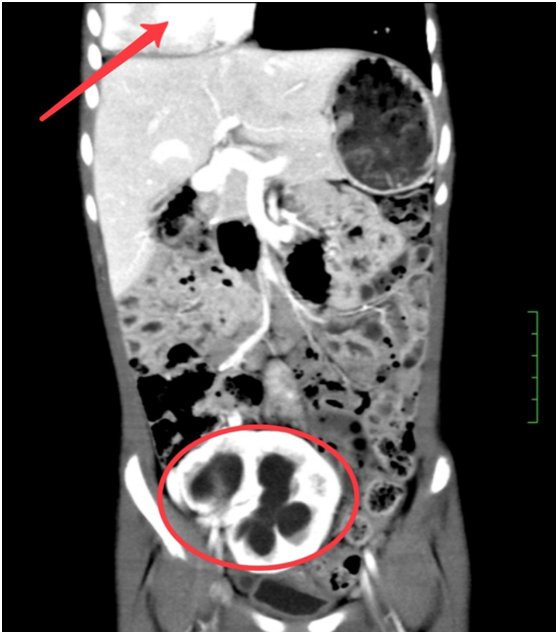

家住长沙望城区的熙熙5岁了还经常尿裤子,常年纸尿裤不离身。家人总以为是孩子年龄小自控力差,没有引起重视。直到体检发现,她本该如小孩拳头大小的右肾因积水胀得像个大苹果。检查还意外发现,她有多种先天发育异常,左肾和右肺先天缺如,本应长在左侧胸腔的心脏也偏到了右边。熙熙是全身多器官位置及发育异常患者,目前国内外尚无相关报道及具体命名此病症。家人表示,熙熙因为这些先天缺陷,从小就体弱多病,是医院的“常客”,得个普通感冒也要十几二十天才能痊愈。